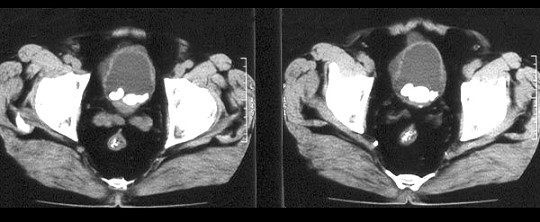

- 单项选择题男,58岁。大量无痛肉眼血尿伴血凝块1天,排尿困难1天。检查:血压120/75mmHg,脉搏82次/分,耻骨上及脐下压痛,叩诊浊音。

本患者以下诊断中哪种疾病的可能性不大() A、膀胱肿瘤

B、肾癌

C、膀胱结石

D、肾盂肿瘤

E、前列腺增生症

- C